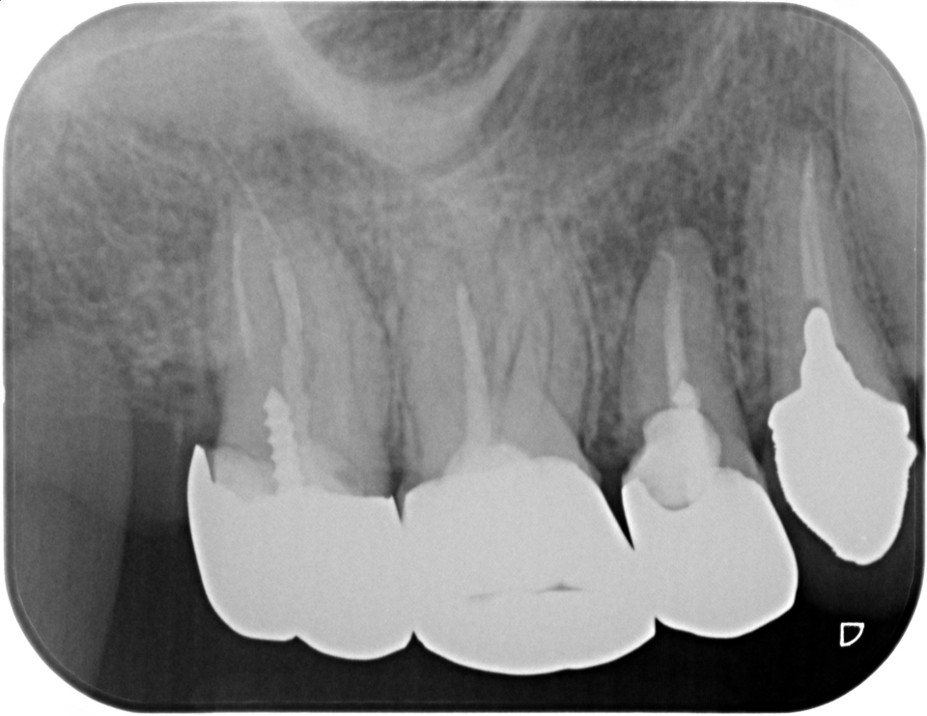

症例2

| 項目 | 詳細 |

|---|---|

| 患者様データ | 50代 女性 |

| 来院時の主訴 | 「左上の歯の周辺から膿が出て臭う。」 |

| 医院の診断 | 虫歯の再発、慢性根尖性歯周炎 |

| 通院期間 | 6ヶ月 |

| 来院回数 | 10回 |

| 治療費 | 580,000円(税抜) 《内訳》 精密感染根管治療80,000円(小臼歯)+100,000円(大臼歯)、ファイバーポストコア20,000円×2、セラミックブリッジ360,000円 |

| リスクと副作用 | ①根管治療歯は長期的には破折するリスク ②メインテナンスが必要 |

| ココがこだわりのポイント☝ |

ラバーダム防湿とマイクロスコープを使用して丁寧に治療を行いました。 再根管治療のため、殺菌性があり歯を補強することのできる根管充填材料を使用しています。 |